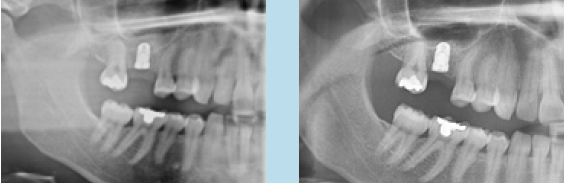

Je nach Implantathersteller stehen Gingivaformer mit unterschiedlichen Durchmessern für ein und denselben Implantatdurchmesser zur Verfügung. In der täglichen Praxis wird zu selten von dieser Möglichkeit Gebrauch gemacht, die Diskrepanz zwischen dem schmalen Diameter der Implantatschulter und dem breiteren physiologischen Durchtrittsprofil einer Molarenkrone bereits bei der Freilegung zu überbrücken.

Unabhängig, ob digital oder analog vorgegangen wird, ist bei der Einbringung der Abformpfosten bzw. Scanbodies darauf zu achten, dass diese sich nicht berühren oder die Nachbarzähne touchieren. Liegen Freilegung und Implantation zeitlich weit auseinander und wurde die Lücke nicht provisorisch versorgt, kann es zum Aufwandern der Nachbarzähne kommen (Abb. 14–17). In diesem Fall ist es notwendig, die Abformpfosten zu beschleifen oder das Aufwandern kieferorthopädisch zu behandeln.

Cave: Veränderungen an den Okklusalflächen durch provisorische Füllungen oder Kronen bei fehlendem Lückenersatz können zu Zahnbewegungen in die Lücke führen. Das Tragen eines nächtlichen Retainers in Form einer Miniplastschiene kann dies verhindern.